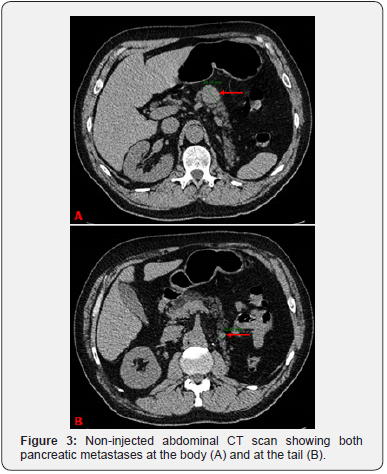

Clear cell renal cell carcinoma represents up to 90% of adult kidney cancers. Risk factors include mainly smoking and obesity [3]. The tumor is usually unilateral. In case of bilateral localization, a hereditary disease should be suspected and the surgical approach should be conservative [4] (Figure 3-5).